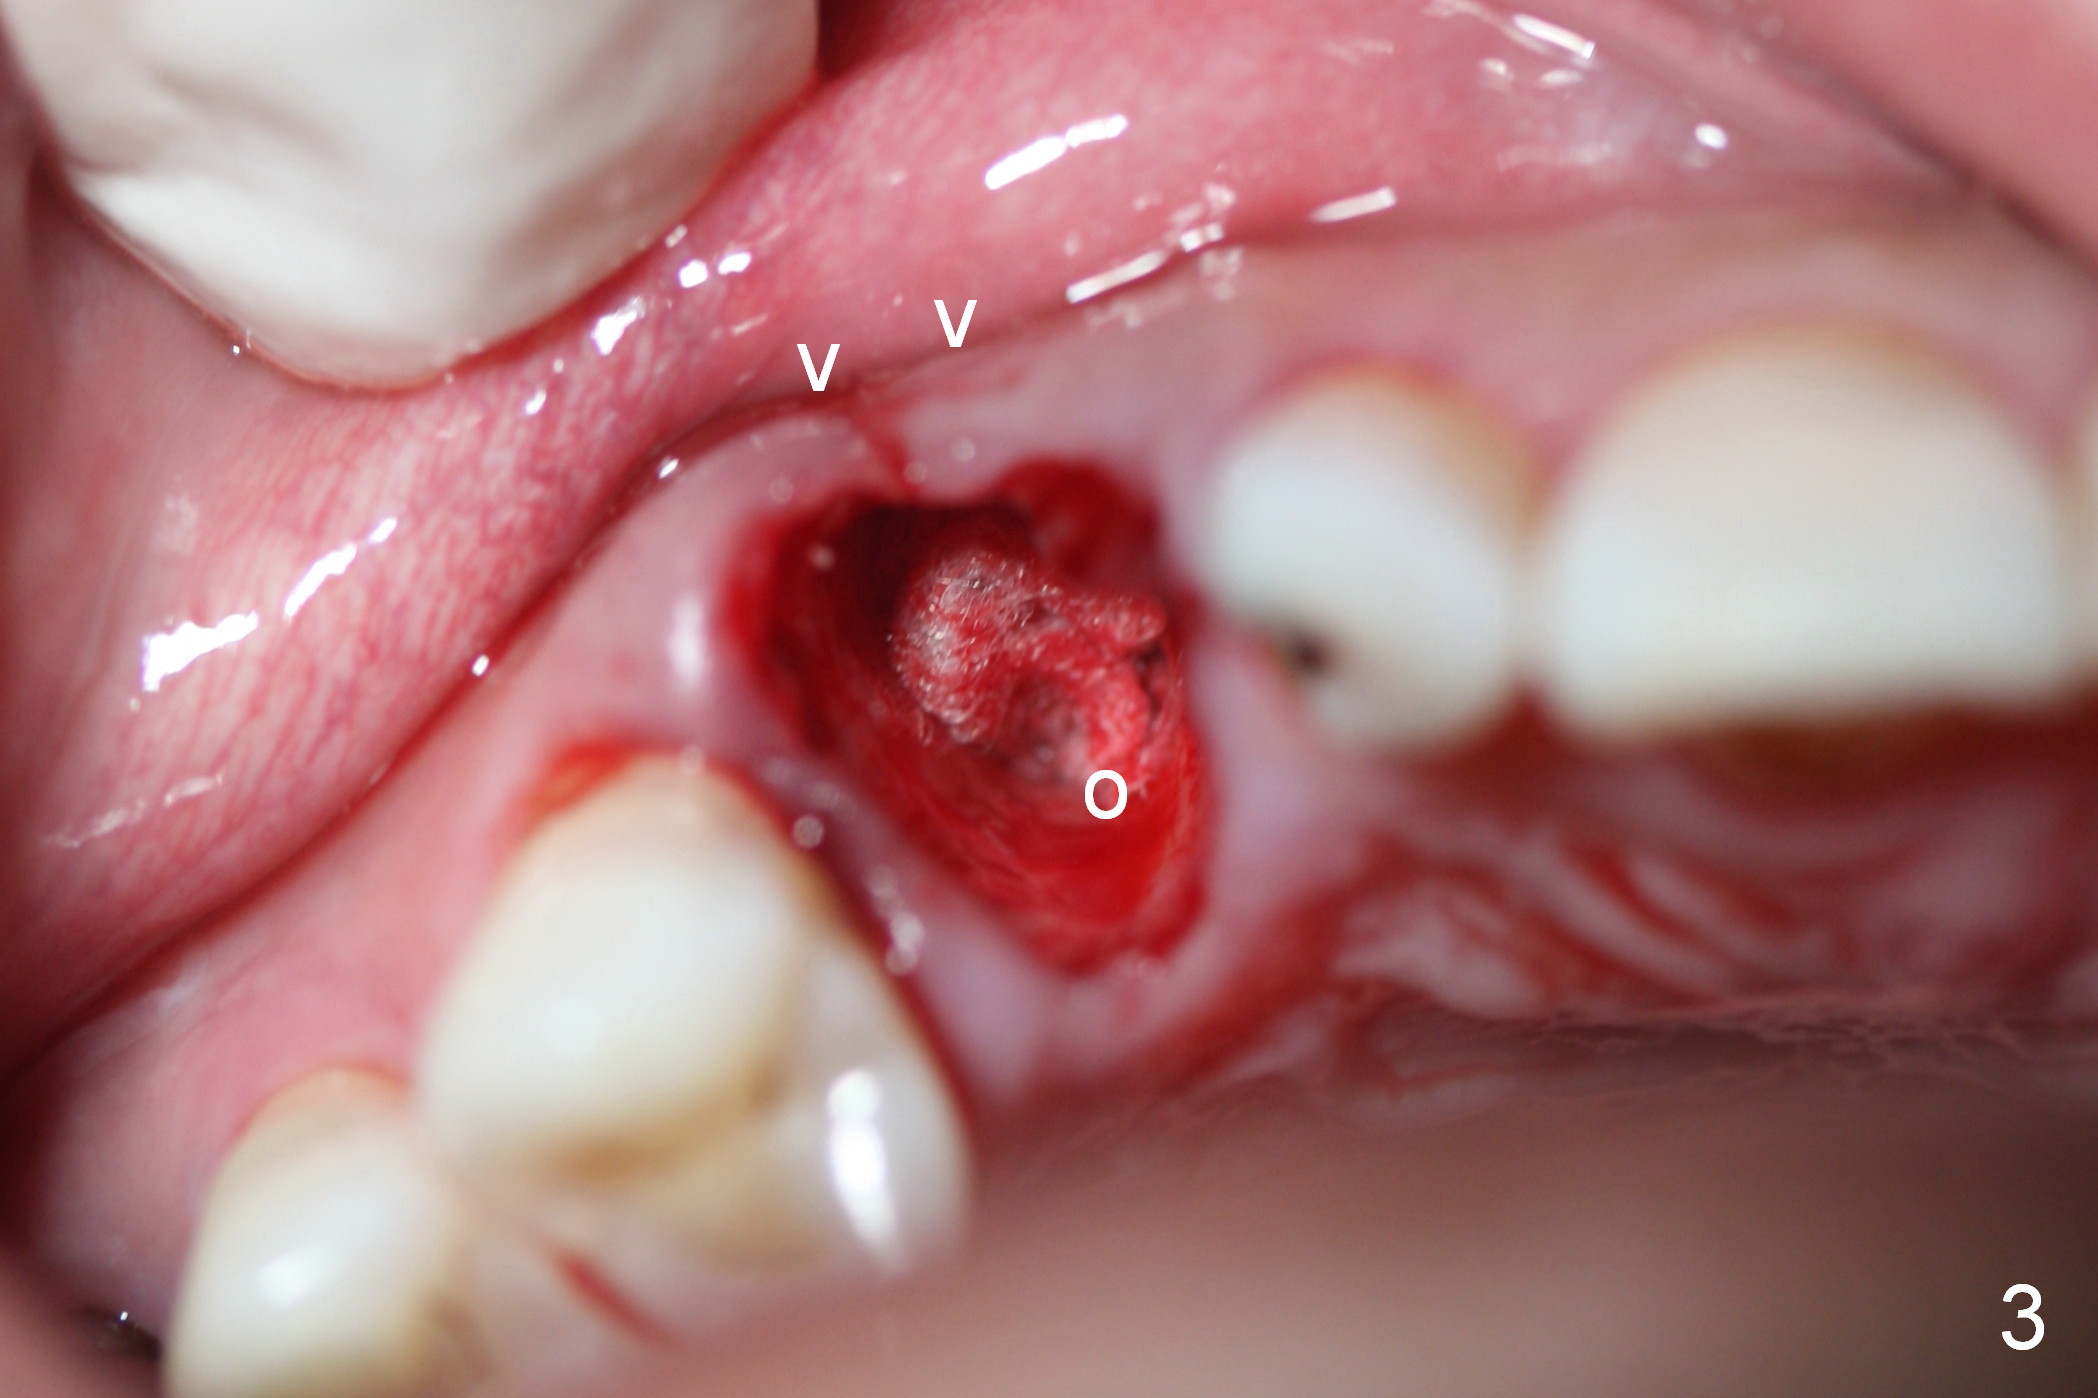

While the periodontal ligament is being severed with Proximators (periotomes), the tooth #6 is found closer to the tooth #5 (Fig.1,2). When the tooth is extracted, an osteotomy is initiated slightly mesially in the palatal wall of the socket (Fig.3 O).